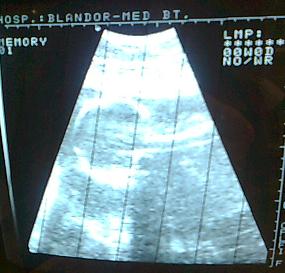

Poci: több ilyen kismamit is ismerek így fórumon keresztül, akinek rövidülés volt, sőt volt akinek valamelyik méhszája is nyitva volt. Egyikkel se lett soha semmi gond, nálatok se lesz.